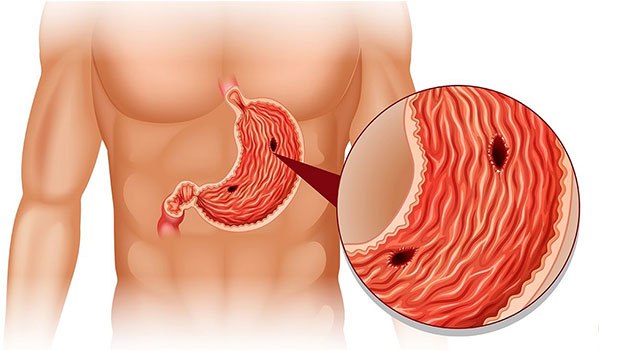

درمان زخم معده و درد مفاصل:

درمان زخم معده:

1. ضد التهاب: هلیله سیاه دارای خواص ضد التهابی است که میتواند به کاهش التهاب در دیواره معده کمک کند.

2. آنتیاکسیدان: این گیاه دارای ترکیبات آنتیاکسیدانی است که میتوانند به حفاظت از سلولهای معده در برابر آسیبهای اکسیداتیو کمک کنند.

3. تقویت سیستم گوارشی: هلیله سیاه ممکن است به بهبود عملکرد سیستم گوارشی و تسهیل هضم کمک کند.